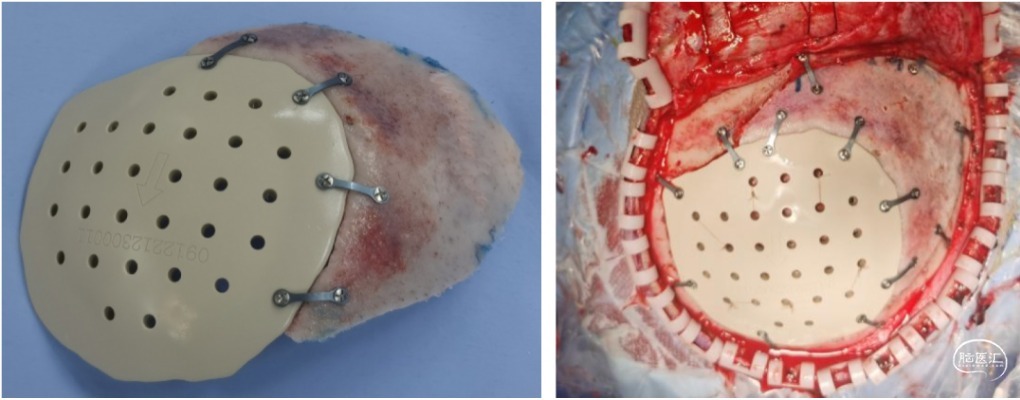

颅骨修补:PEEK修补材料与扩大骨瓣固定,一并复位

PEEK材料,全称聚醚醚酮,优点在于:嵌入式,减少了覆盖式颅骨修补材料的凹凸感;力学性能强于自体骨,不会出现变形断裂;射线透过性好,核磁CT检查无伪影;不受冷热影响,对于头皮较薄的儿童尤为适合,而且是非金属,减少患儿未来心理影响。